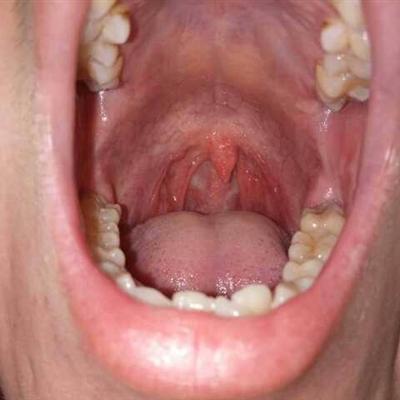

Second: there are many patients with bad breath. Generally, if they have dental problems, such as gingivitis, periodontitis, oral mucositis, and bad breath caused by tooth decay, periodontal disease, caries and other factors, the problem is quite serious. Timely treatment is the key to the problem.

Third: halitosis is generally caused by not paying attention to oral hygiene, which is an important oral problem. Many people will also have halitosis if they have stomach heat.